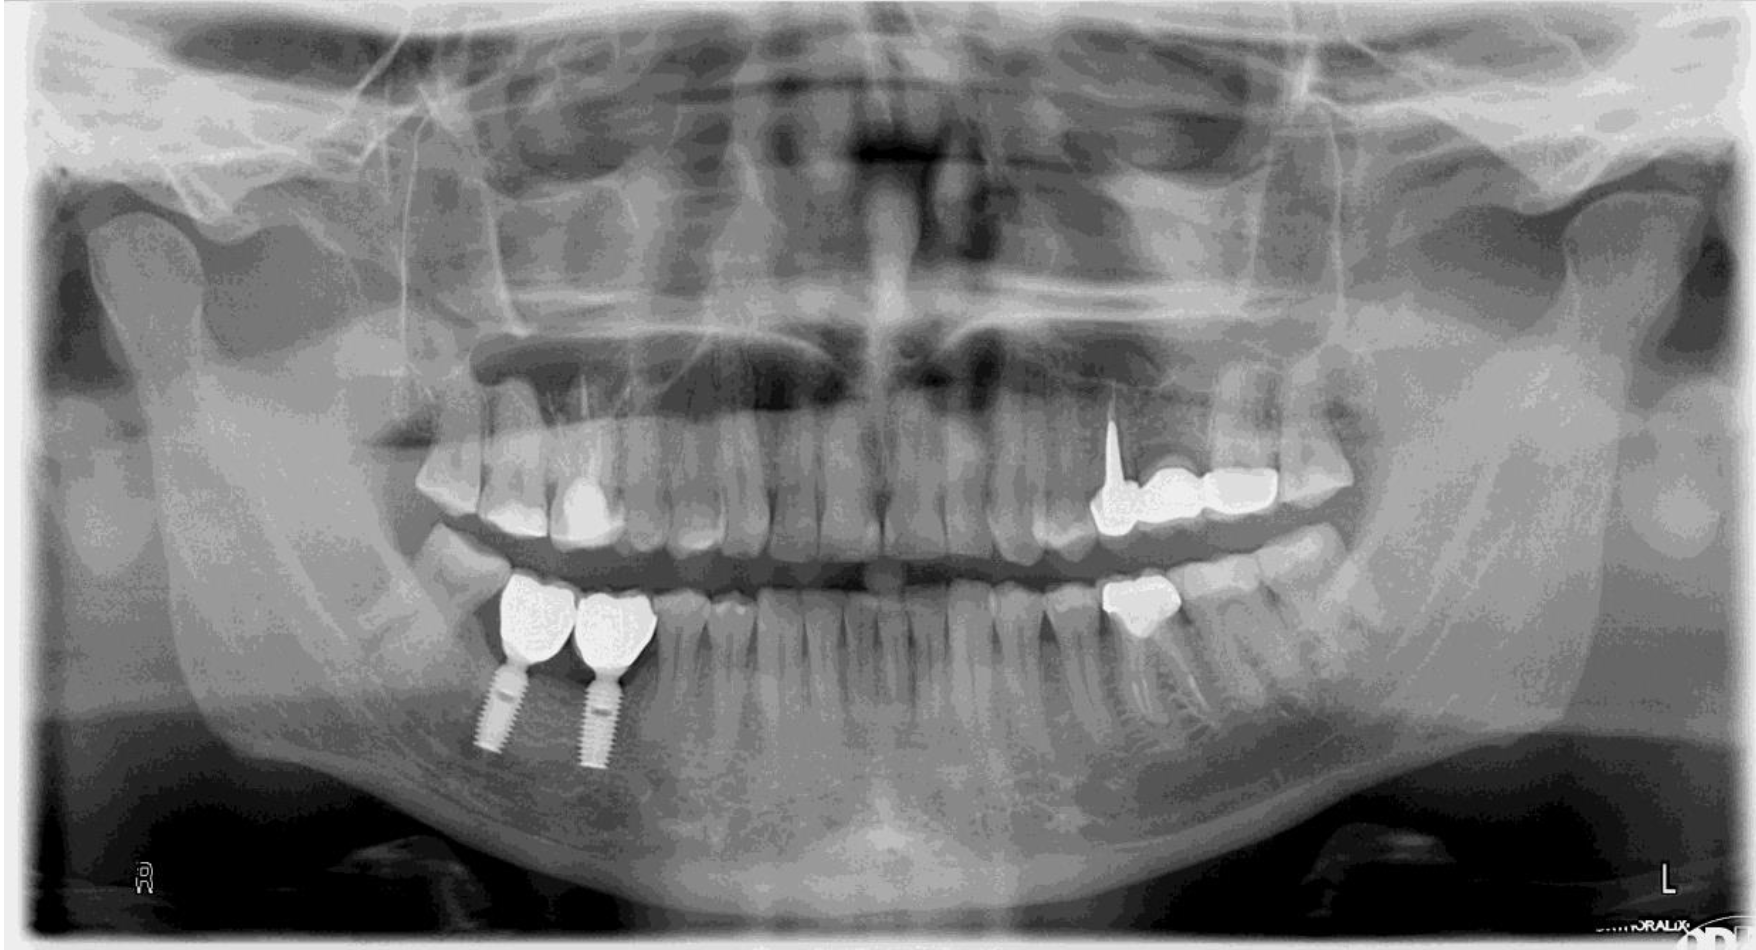

Implanty zębowe (implanty dentystyczne) to innymi słowy zamienniki korzenia zębowego, które umiejscawiane są w kości żuchwy bądź szczęki. Ich osadzenie pozwala stworzyć koronę, most lub protezę, która pozwoli uzupełnić braki w uzębieniu. Implanty zębowe to opcja, dzięki której nie maskujemy niedoskonałości, a uzupełniamy uśmiech w prawidłowo funkcjonujący oraz prezentujący się naturalnie nowy ząb. Wykonanie z biozgodnego tytanu sprawia, że organizm doskonale go przyjmuje, a prawidłowo chirurgicznie wszczepiony implant zostaje obudowany przez kość (tzw. osteointegracja), dzięki czemu ząb jest stabilny i mocno osadzony.

Sam implant na tym etapie nie uzupełnia braku w uzębieniu. Pełna funkcjonalność zapewniona jest dopiero po zamocowaniu w implancie korony, mostu lub protezy. W części protetycznej uzupełniania uśmiechu – wykonywanej po pełnym procesie osteointegracji – możliwe jest założenie nowego zęba lub zębów.